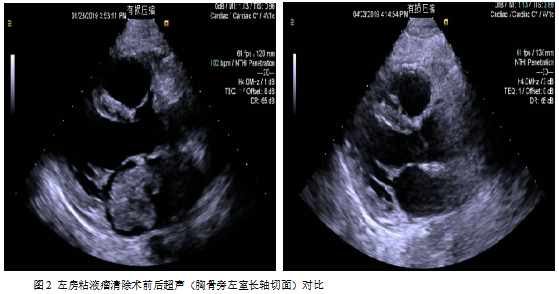

诊断:左房占位主要根据间断胸闷憋喘伴咳嗽等临床症状结合影像学主要是超声心动图评估作出诊断;根据超声心动图检查,可见左房占位蒂附着于房间隔左房面与卵圆窝相应的位置,单发,通过形态及活动度,考虑为单纯粘液瘤。

手术:目前左房粘液瘤患者手术指征粘液瘤可阻塞瓣膜开口导致心力衰竭或心跳骤停,瘤栓脱落导致脑检塞等也可以引起死亡。因此,一且确诊,立即争取手术治疗。一般心脏患者如有长期发热、心力衰竭、贫血、血沉增快等现象,须延缓手术。但对心脏粘液瘤患者需具体分析,否则可能丧失手术机会。如有高热、血沉快,全身症状为主要表现,并且考虑是由粘液瘤引起,应立即手术,摘除肿瘤能使体温下降、心率变慢、血沉恢复正常、心衰得到控制。如果感染性心内膜炎引起的高热、心力衰過,不宜急于手术,应该控制高热、心衰后手术,以免发生严重的并发症[1-2]。该患者左房占位病变巨大,且血流动力学不稳定,肿物随左心室舒张通过二尖瓣从左房脱入左室,左心室收缩又返流回左房,因粘液瘤部分阻塞二尖瓣口,随体位变化有间歇性昏厥的患者,我们选择严格限制卧床体息,应用静脉滴注多巴胺强心维持血压,同时给予利尿药减轻肺水肿,准备急症手术。

术后病理:(左心房肿瘤)肿瘤细胞呈圆形、梭形及星芒状,单个散在或呈条索状排列,其周可见空晕,间质富于粘液,部分肿瘤细胞围绕血管周围排列,血管扩张充血伴大片出血。形态符合粘液瘤。